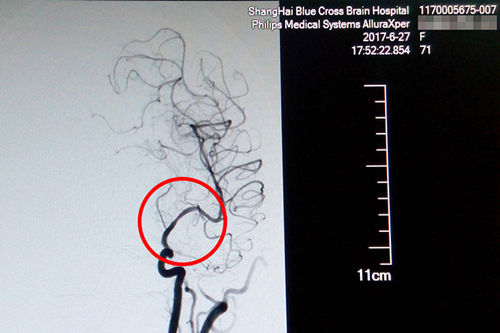

站在手术台前的李主任,表现出的是与平日不同的冷静和沉着。经术中精准测量发现,患者盛阿姨血管狭窄达到了77%,血管非常狭窄,使放置球囊扩张支架的难度更大。好在李主任积累了丰富的DSA手术经验,经过仔细小心的操作,导丝成功地通过了狭窄的血管。李主任用他的“血管艺术”使濒临枯萎的血管重新绽放出了生命的活力,最终原本非常狭窄的血管腔顺利张开了:“……将球囊扩张支架置入狭窄处,观察后准确释放球囊扩张支架,再造行3D造影,显示血管扩张,血流恢复正常。(摘自术后小结)”。

术后DSA影像显示,患者血管狭窄部位血流恢复正常